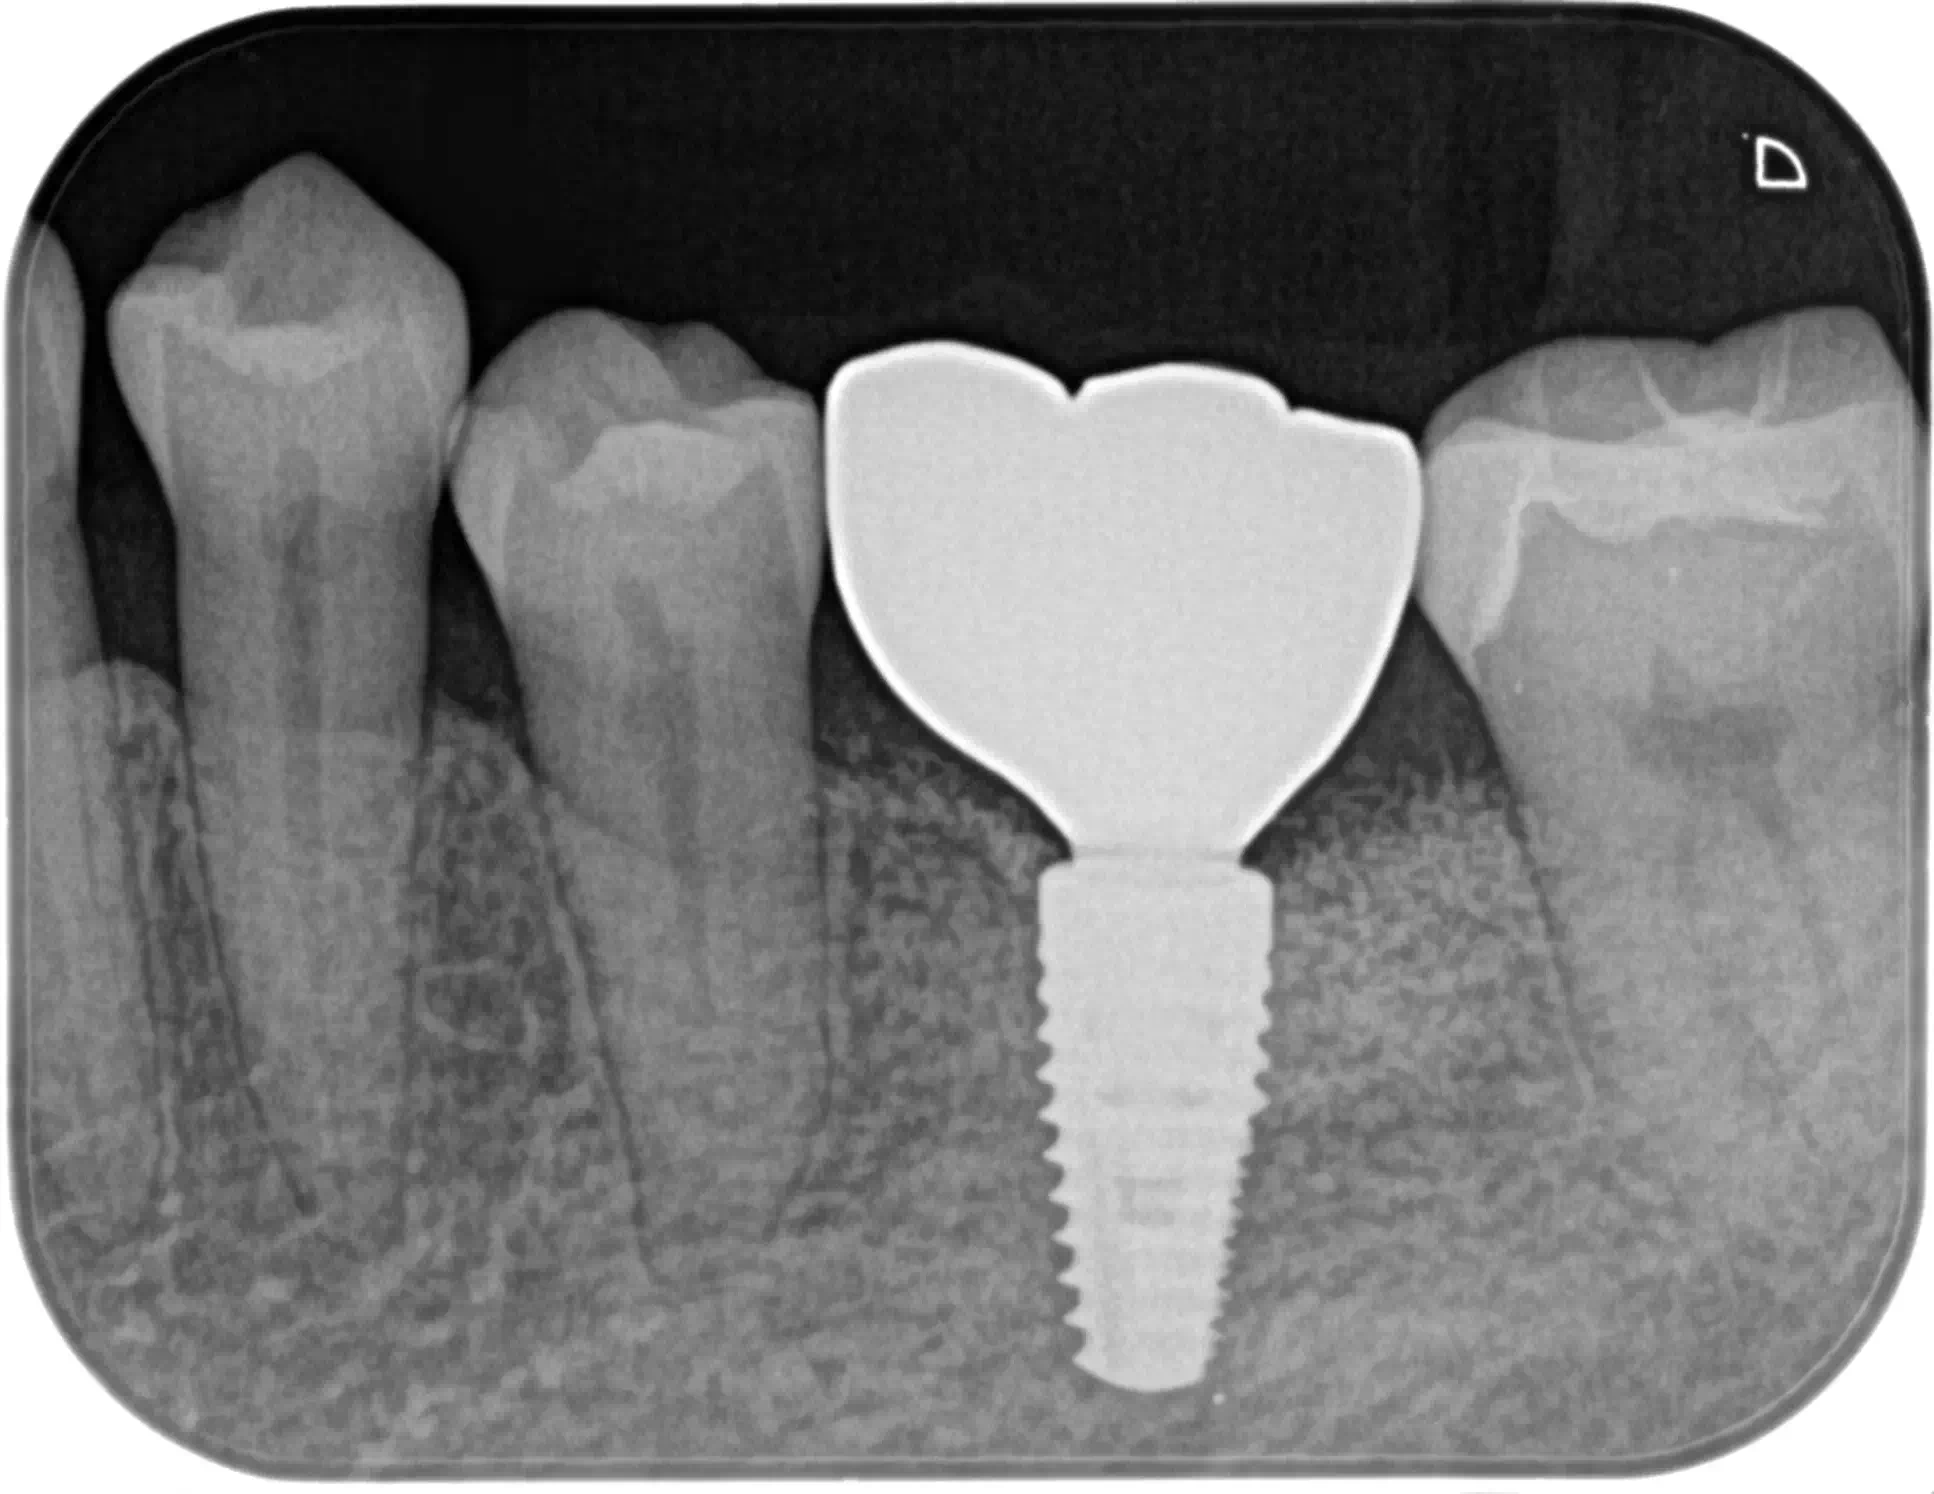

CASE HOME CASE 2025/10/21 抜歯即時埋入・即時荷重 症例 2025/10/21 GBR① 2025/10/21 インプラント 症例② 2025/10/21 インプラント 症例① 2025/10/21 矯正歯科 症例 2025/10/21 審美歯科 症例② 2025/10/21 審美歯科 症例① 2025/10/21 ガミースマイル 症例 2025/10/21 歯肉再生 症例② 2025/10/21 歯肉再生 症例① 2025/10/21 虫歯症例